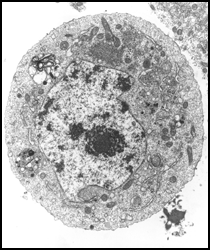

Vírus da dengue

(Ortrud Monika Barth/ Departamento de

Virologia/IOC/Fiocruz)